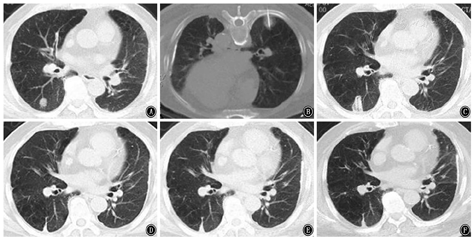

近年来,关于介入消融治疗早期结节型肺癌的报道逐渐增多,主要应用于因心肺功能差等无法手术的患者。研究显示,经皮RFA治疗Ⅰ期NSCLC可有效控制肿瘤进展,获得较为满意的生存率[11]。MWA治疗Ⅰ期NSCLC也获得了较好的临床疗效,研究报道MWA治疗老年早期NSCLC,5年局部控制率可达63.9%[12];还有研究发现,病灶>3.5 cm是MWA治疗后复发的独立危险因素,但复发后再次行MWA治疗,可获得与未复发者相仿的预后[13],该结果提示MWA可重复操作且不影响预后。此外,有文献报道经皮冷冻消融治疗Ⅰ期NSCLC的5年无进展生存率可达(87.9±9.0)%[14]。这些研究中并无严重并发症的报道,提示经皮介入消融治疗早期肺癌安全、有效。本中心近年来也对部分符合适应证的实性结节型肺癌进行了消融治疗,典型病例见图1。